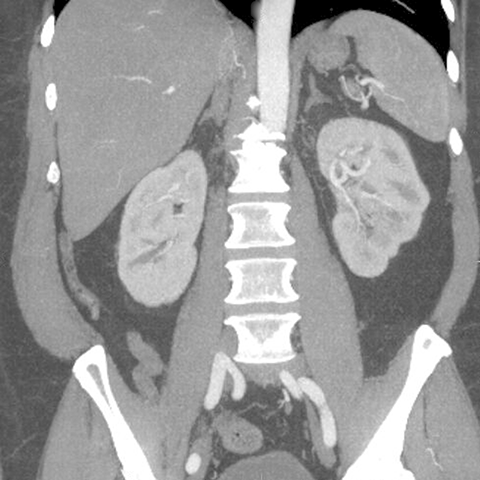

Normal Appendix, CT (coronal) [1 of 6]